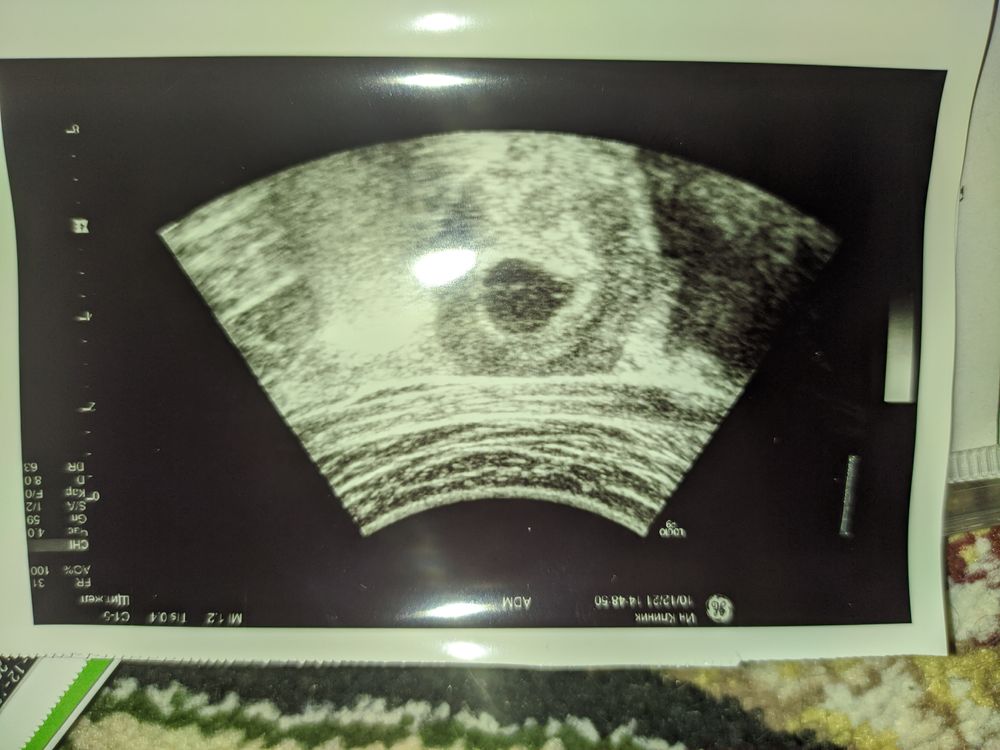

Ангелина Жукова, 4 дня назад УЗИ было такое

И вроде как там был эмбрион (делала вагинально у другого узиста)

Светлана Сопчинская, Делала 4 дня назад - посмотрите выше фото УЗИ - был 11мм ПЯ и четко визуально видно МЕШОЧЕК и эмбриончик...